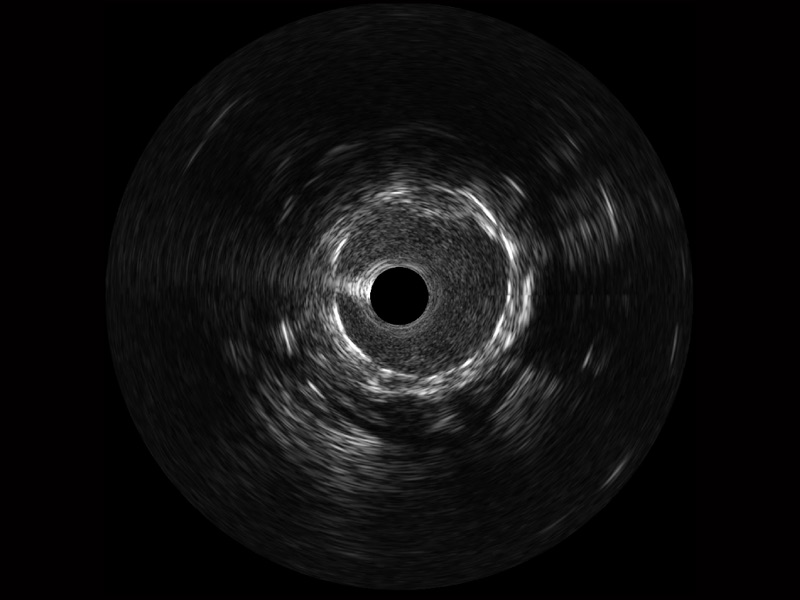

• 新葡的京集团8814检测站宽频IVUS图像

• 传统IVUS图像

对比传统IVUS导管成像,新葡的京集团8814检测站宽频IVUS图像的近场支架梁显影更细腻,远场中膜外血管仍清晰可辨,兼顾远中近,兼顾分辨力与穿透深度